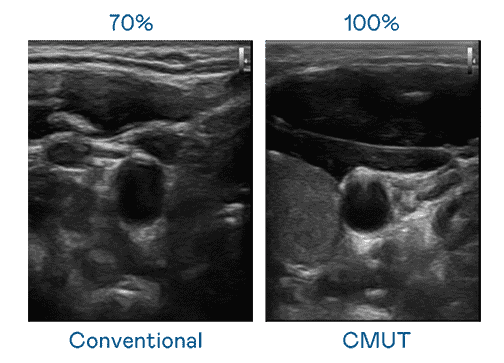

CMUT 技术是一种用电容式微机电元件来产生超音波讯号的技术。。与传统 PZT 压电式技术相比,,,,CMUT 频宽增加 30%,,,,更宽频的超音波讯号让影像解析度大幅提升,,,是实现高影像品质医疗超音波扫描、、、促进精准医疗发展的关键技术。。。。

大频宽带来超清晰影像

超音波影像的解析度高低,,,,首先取决于探头能发出的讯号频宽。。。尊龙集团 CMUT 可提供高清晰的超音波讯号,,,提供高频宽、、、高灵敏度、、影像纹理细节更高的超音波影像,,,,协助医护人员缩短影像判读时间及利用精准的医疗影像进行诊断。。。。